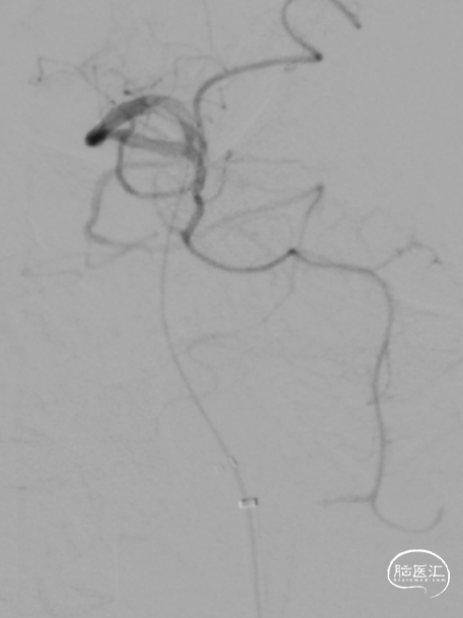

急诊DSA:Ⅱ型弓,基底动脉AICA以远未见显影。

加奇Tethys®中间导引导管到位,明确既往支架位置。但中间导管通过困难。

微导丝微导管通过闭塞段,在右侧大脑后动脉手推造影证实真腔,明确闭塞段,可见造影剂返流至基底动脉尖部,且证明闭塞确为支架内再狭窄导致闭塞。

释放加奇4.0mm*30mm Syphonet®取栓支架,可见支架通体显影。

第一次取栓后,血管未通,但明确支架内狭窄位置,交换引入头端塑形的300cm 0.014in微导丝,撤出微导管,沿微导丝引入2.0mm*15mm Sprinter球囊,扩张后狭窄明显减轻,但血栓掉落至右侧大脑后动脉起始部。

交换再次引入加奇4.0mm*30mm Syphonet®取栓支架并释放。

第二次拉栓后造影,血管再通,支架内再狭窄处理风险极高,且目前前向血流3级,对比造影时影像支架未有移位。